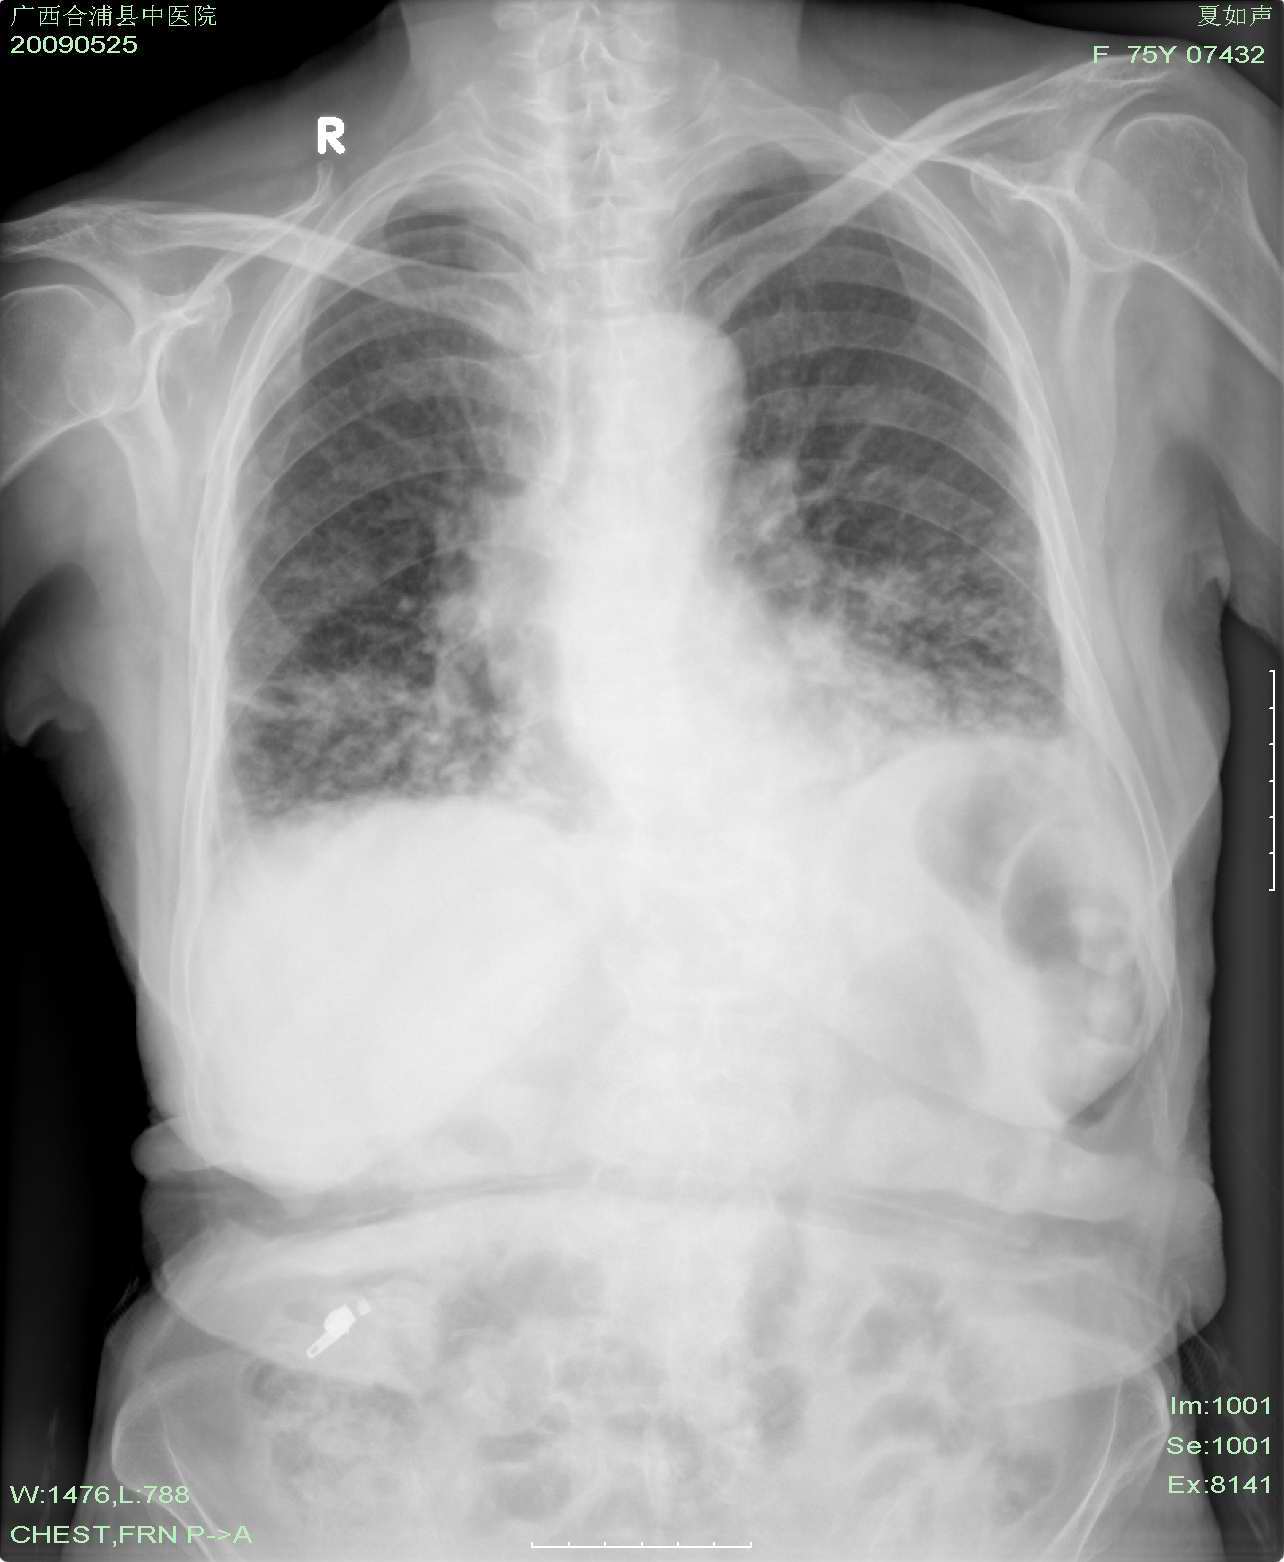

以上是2009-05-25的照片。

以下是引用37度在2009-9-12 11:54:00的发言:[br][br] [br] 支气管扩张合并混合型感染 [br] [br]

以下是引用dyqct在2009-9-12 8:42:00的发言:[br]慢性支气管炎合并间质纤维化、肺气肿、支气管扩张、感染。建议ct进一步检查。

以下是引用黑白光影在2009-9-12 16:43:00的发言:[br]慢支并感染(霉菌?)